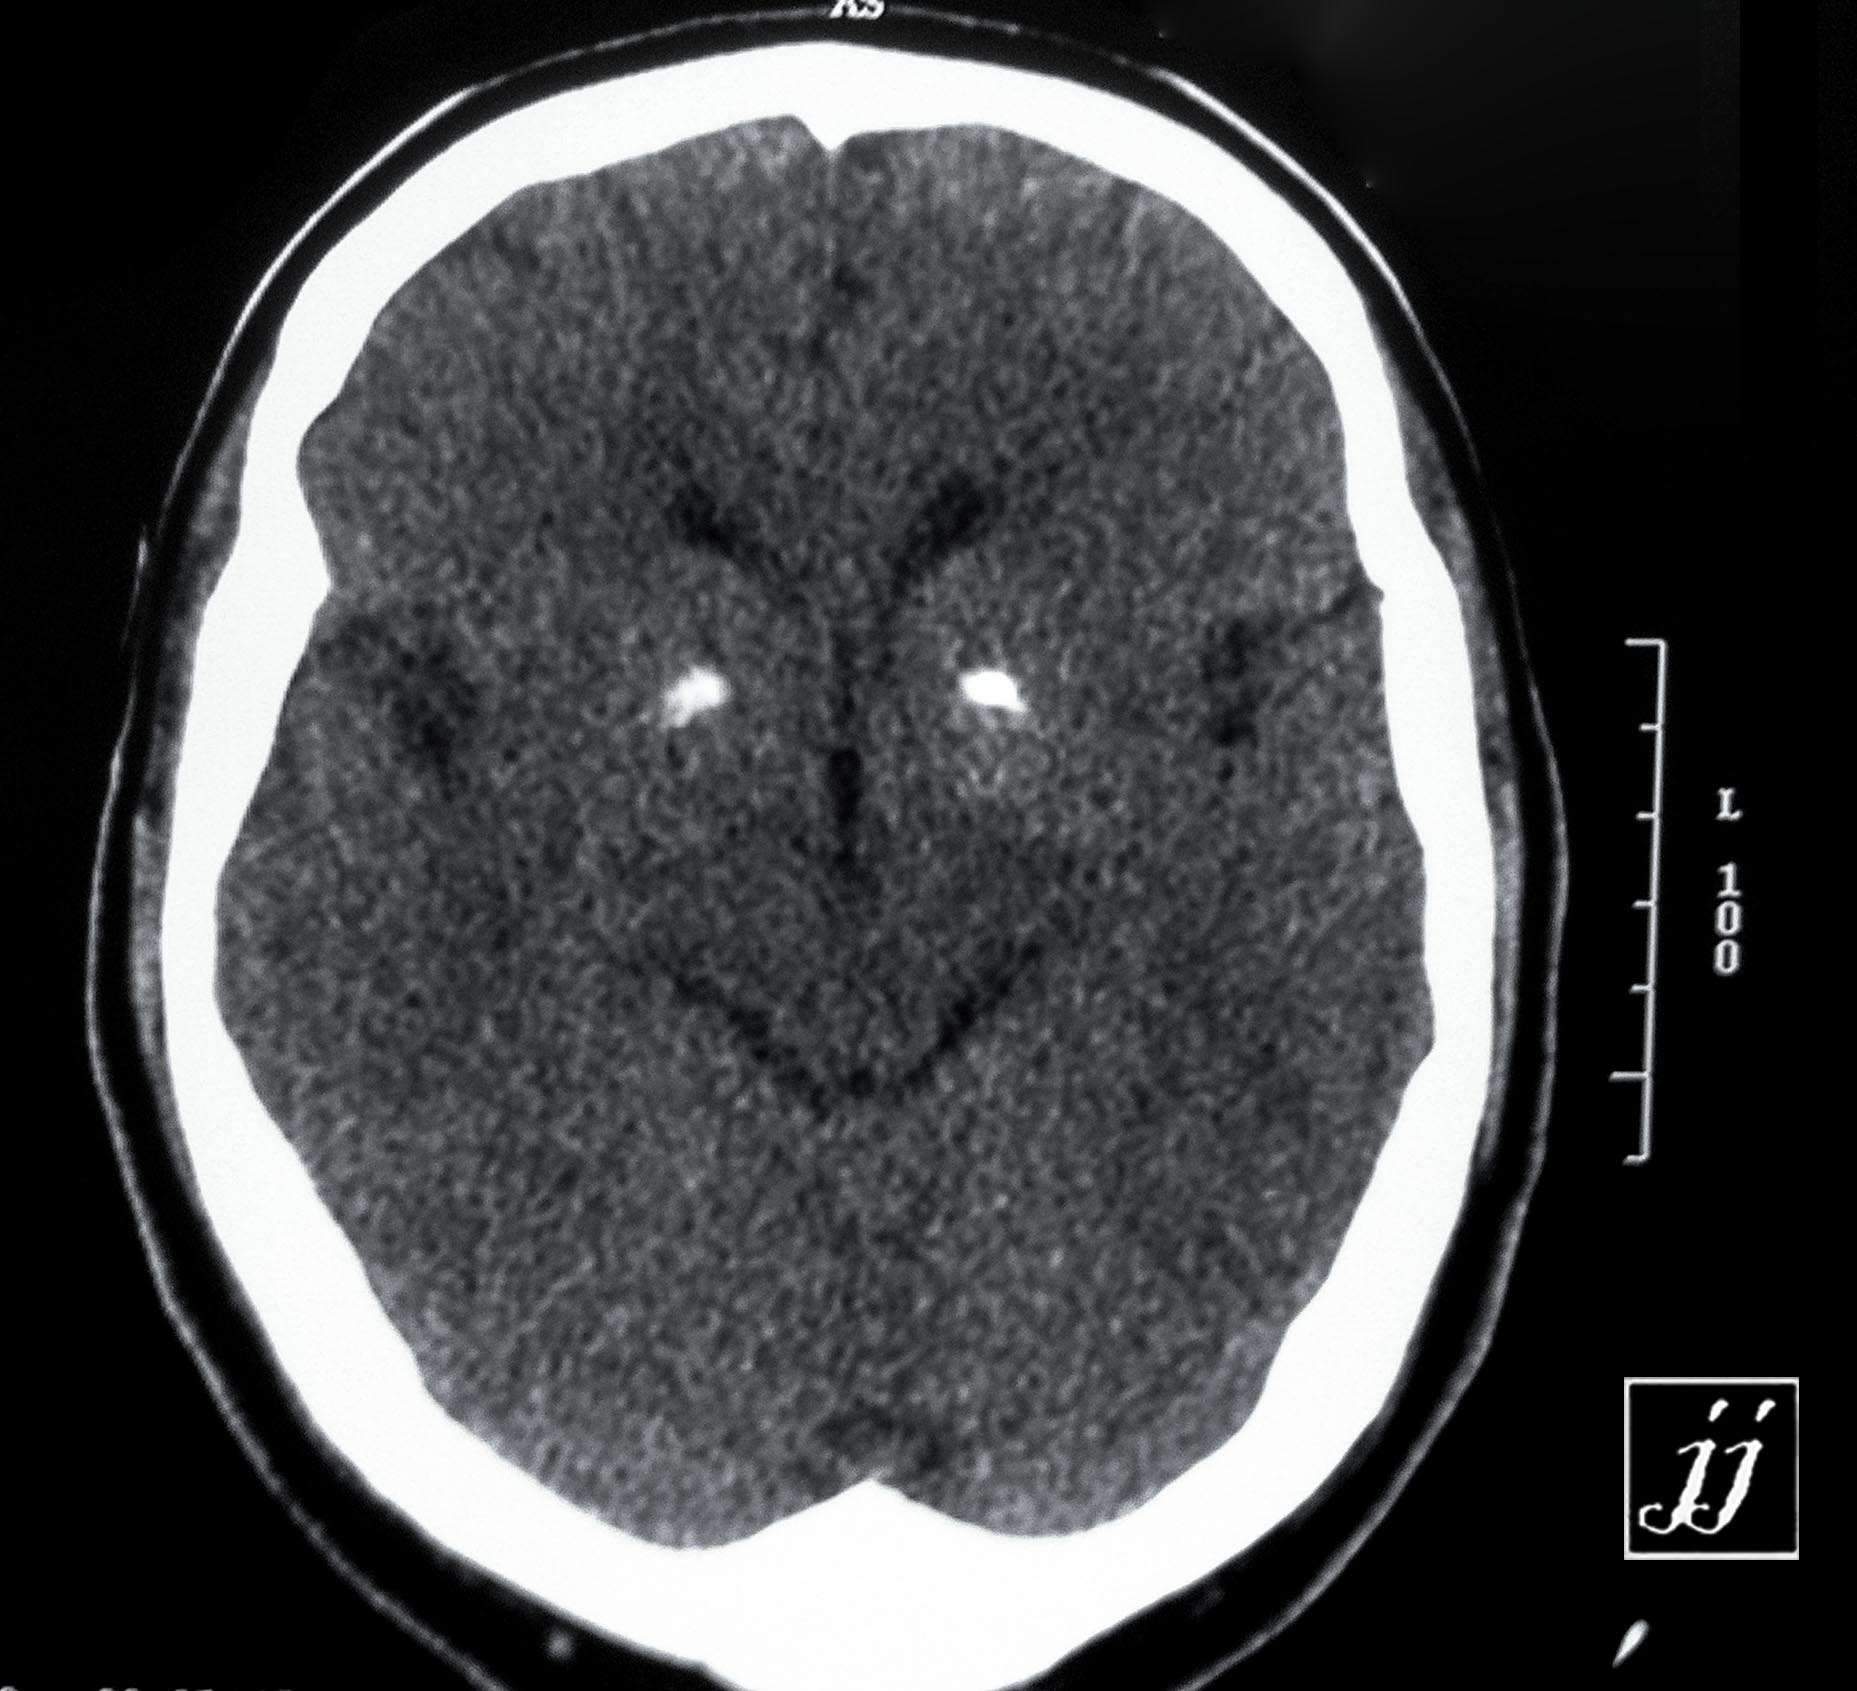

brain- basal ganglia calcification